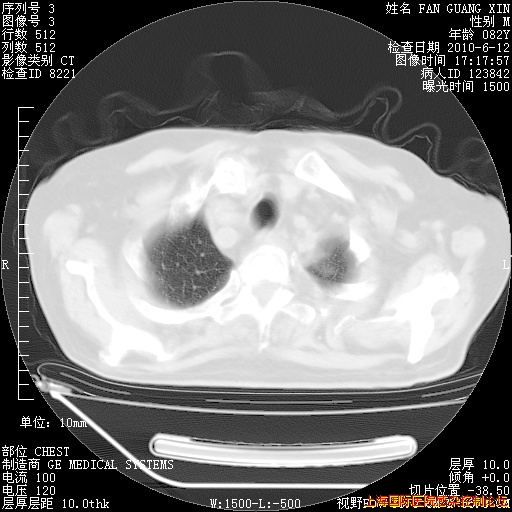

补发6月12日肺部CT肺窗

6月12日肺窗